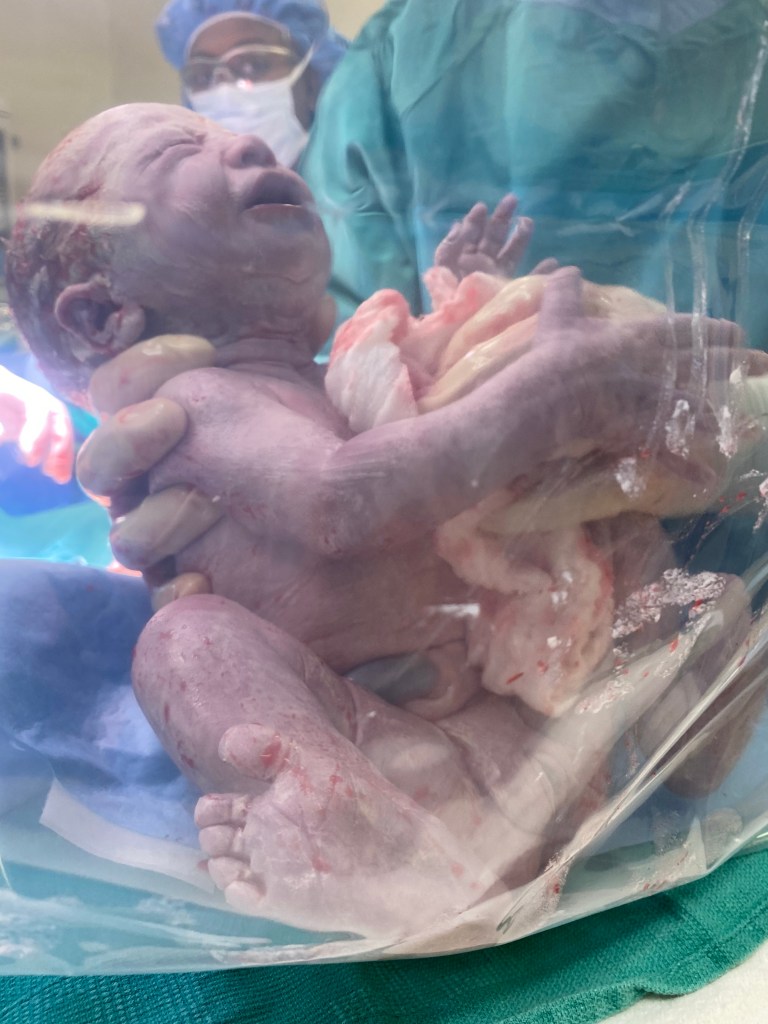

21h52 : Docteur Mansour me montre bébé Eléonore par le plastique transparent du drap placé devant moi! Elle est toute petite!

Puis contrairement à Gabriel ils l’emmènent tout de suite dans une autre salle… Nous attendons un peu perplexe et enfin ils nous la rapporte pour qu’on puisse la prendre dans nos bras.